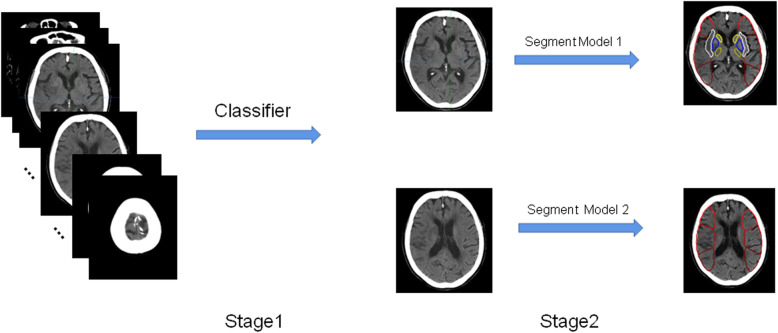

We developed 1 classifier and 2 segmentation models to accomplish the task. The classifier used visual geometry group (VGG) model pre-trained on a large dataset as feature extractor, through which we can fine tune to extract target slices from the CT head series as in stage 1. In stage 2, segment model 1 detects 14 areas in the nucleus mass layer, and segment model 2 detects 6 areas in the nucleus mass upper layer. The segmentation models had the encoder-decoder architecture as U-Net and made better use of features through dense connections (Fig. 2).

Fig. 2.

Flow chart of the software analysis